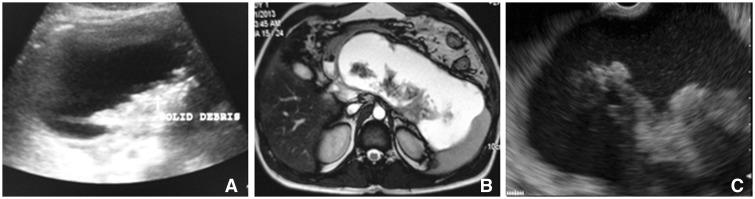

Walled-off pancreatic necrosis (WOPN) is an important complication of acute pancreatitis that is diagnosed by imaging modalities such as endoscopic ultrasound (EUS) or magnetic resonance imaging (MRI), which can clearly visualize necrotic debris. The effectiveness of abdominal ultrasound (USG) in detecting solid debris in WOPN is not clear.

A total of 52 patients (37 males, mean age 38.9 ± 12.6 years) with symptomatic WOPN were prospectively studied using EUS, MRI and USG. These investigations were done at a mean of 11.7 ± 5.5 weeks of onset of acute pancreatitis and within two days.

WOPN was detected by EUS & MRI in all patients, whereas USG could not detect it in 4 (7.6%) patients (3 had predominantly solid WOPN, whereas one had air foci in WOPN). USG, MRI and EUS could detect solid debris in all patients with detectable WOPN. EUS and USG detected <10% debris in 10 (20%) patients, whereas MRI detected <10% debris in 14 (27%) patients. EUS and USG detected 10-40% debris in 33 patients whereas MRI detected 10-40% debris in 30 (58%) patients. More than 40% debris was better characterized on EUS and MRI with both detecting >40% debris in 8 patients (15%) compared to 5 (11%) patients having >40% debris on USG. EUS detected collaterals around WOPN that were not detected on USG or MRI.

USG can characterize the majority of WOPN, with accuracy comparable to that of EUS/MRI. However its limitations are the inability to detect collaterals around WOPN and characterize collections with high solid content or air.